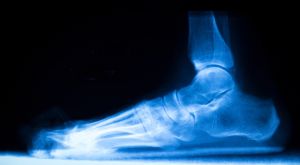

Radiographic Signs of Progression

- X-rays: Collapsed medial arch, talar head uncovering, increased Meary’s angle.